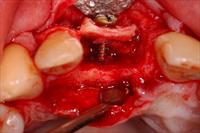

![]() 2. Thin edentulous ridge with cuts made. |